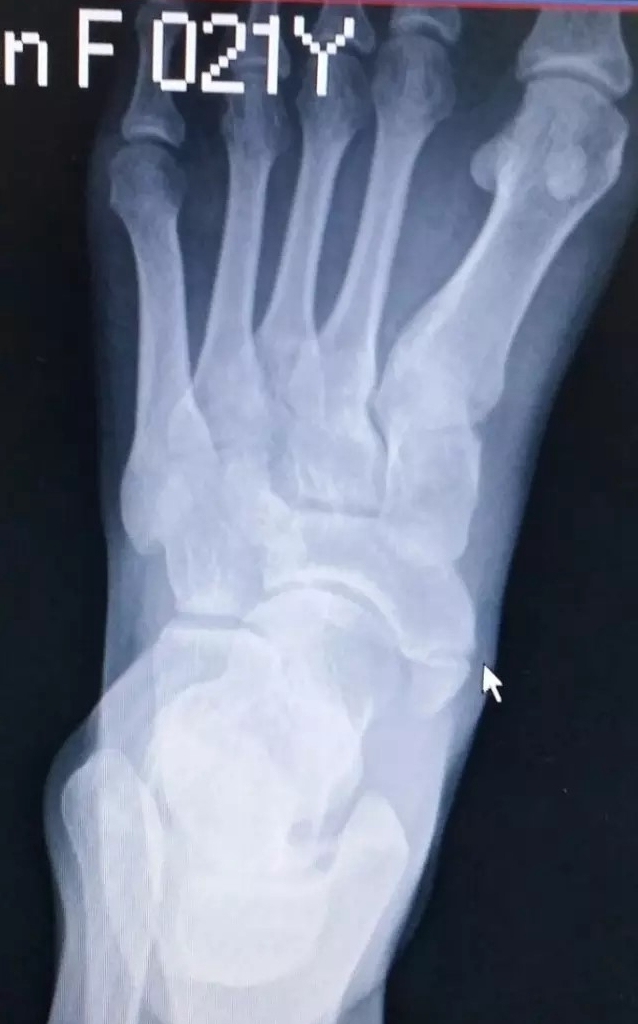

当发生足副舟骨疼痛时,首先要拍X光确诊,并确定分型。

副舟骨损伤多见于青壮年男性,常见发生在足内翻崴脚扭伤后。此时胫骨后肌突然收缩或将在副舟骨上的附着点撕脱。

二型副舟骨是舟骨的一部分,由结节部纤维软骨板分开。进一步分为2A和2B型。